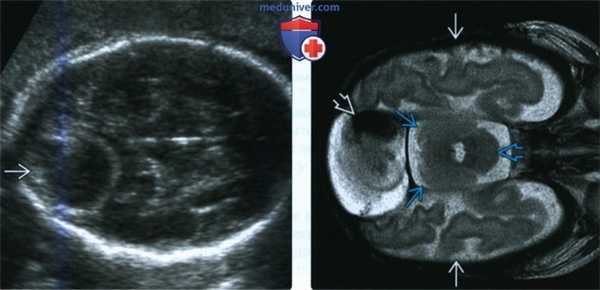

(Слева) В III триместре беременности при стандартном УЗИ в аксиальной плоскости у плода выявляется типичная тромбированная МСТМО в виде четко очерченного экстрааксиального новообразования. Головной мозг не поврежден. Новорожденный был здоров, рос и развивался нормально.

(Справа) При МРТ на Т2-ВИ в аксиальной плоскости у другого новорожденного с благоприятным исходом видны нормальные большие полушария головного мозга, мозжечок и ствол мозга с небольшим сморщенным сгустком крови внутри МСТМО. На 20-й неделе гестации образование занимало почти 1/2 объема черепа. Оно сморщивалось по мере роста головного мозга.